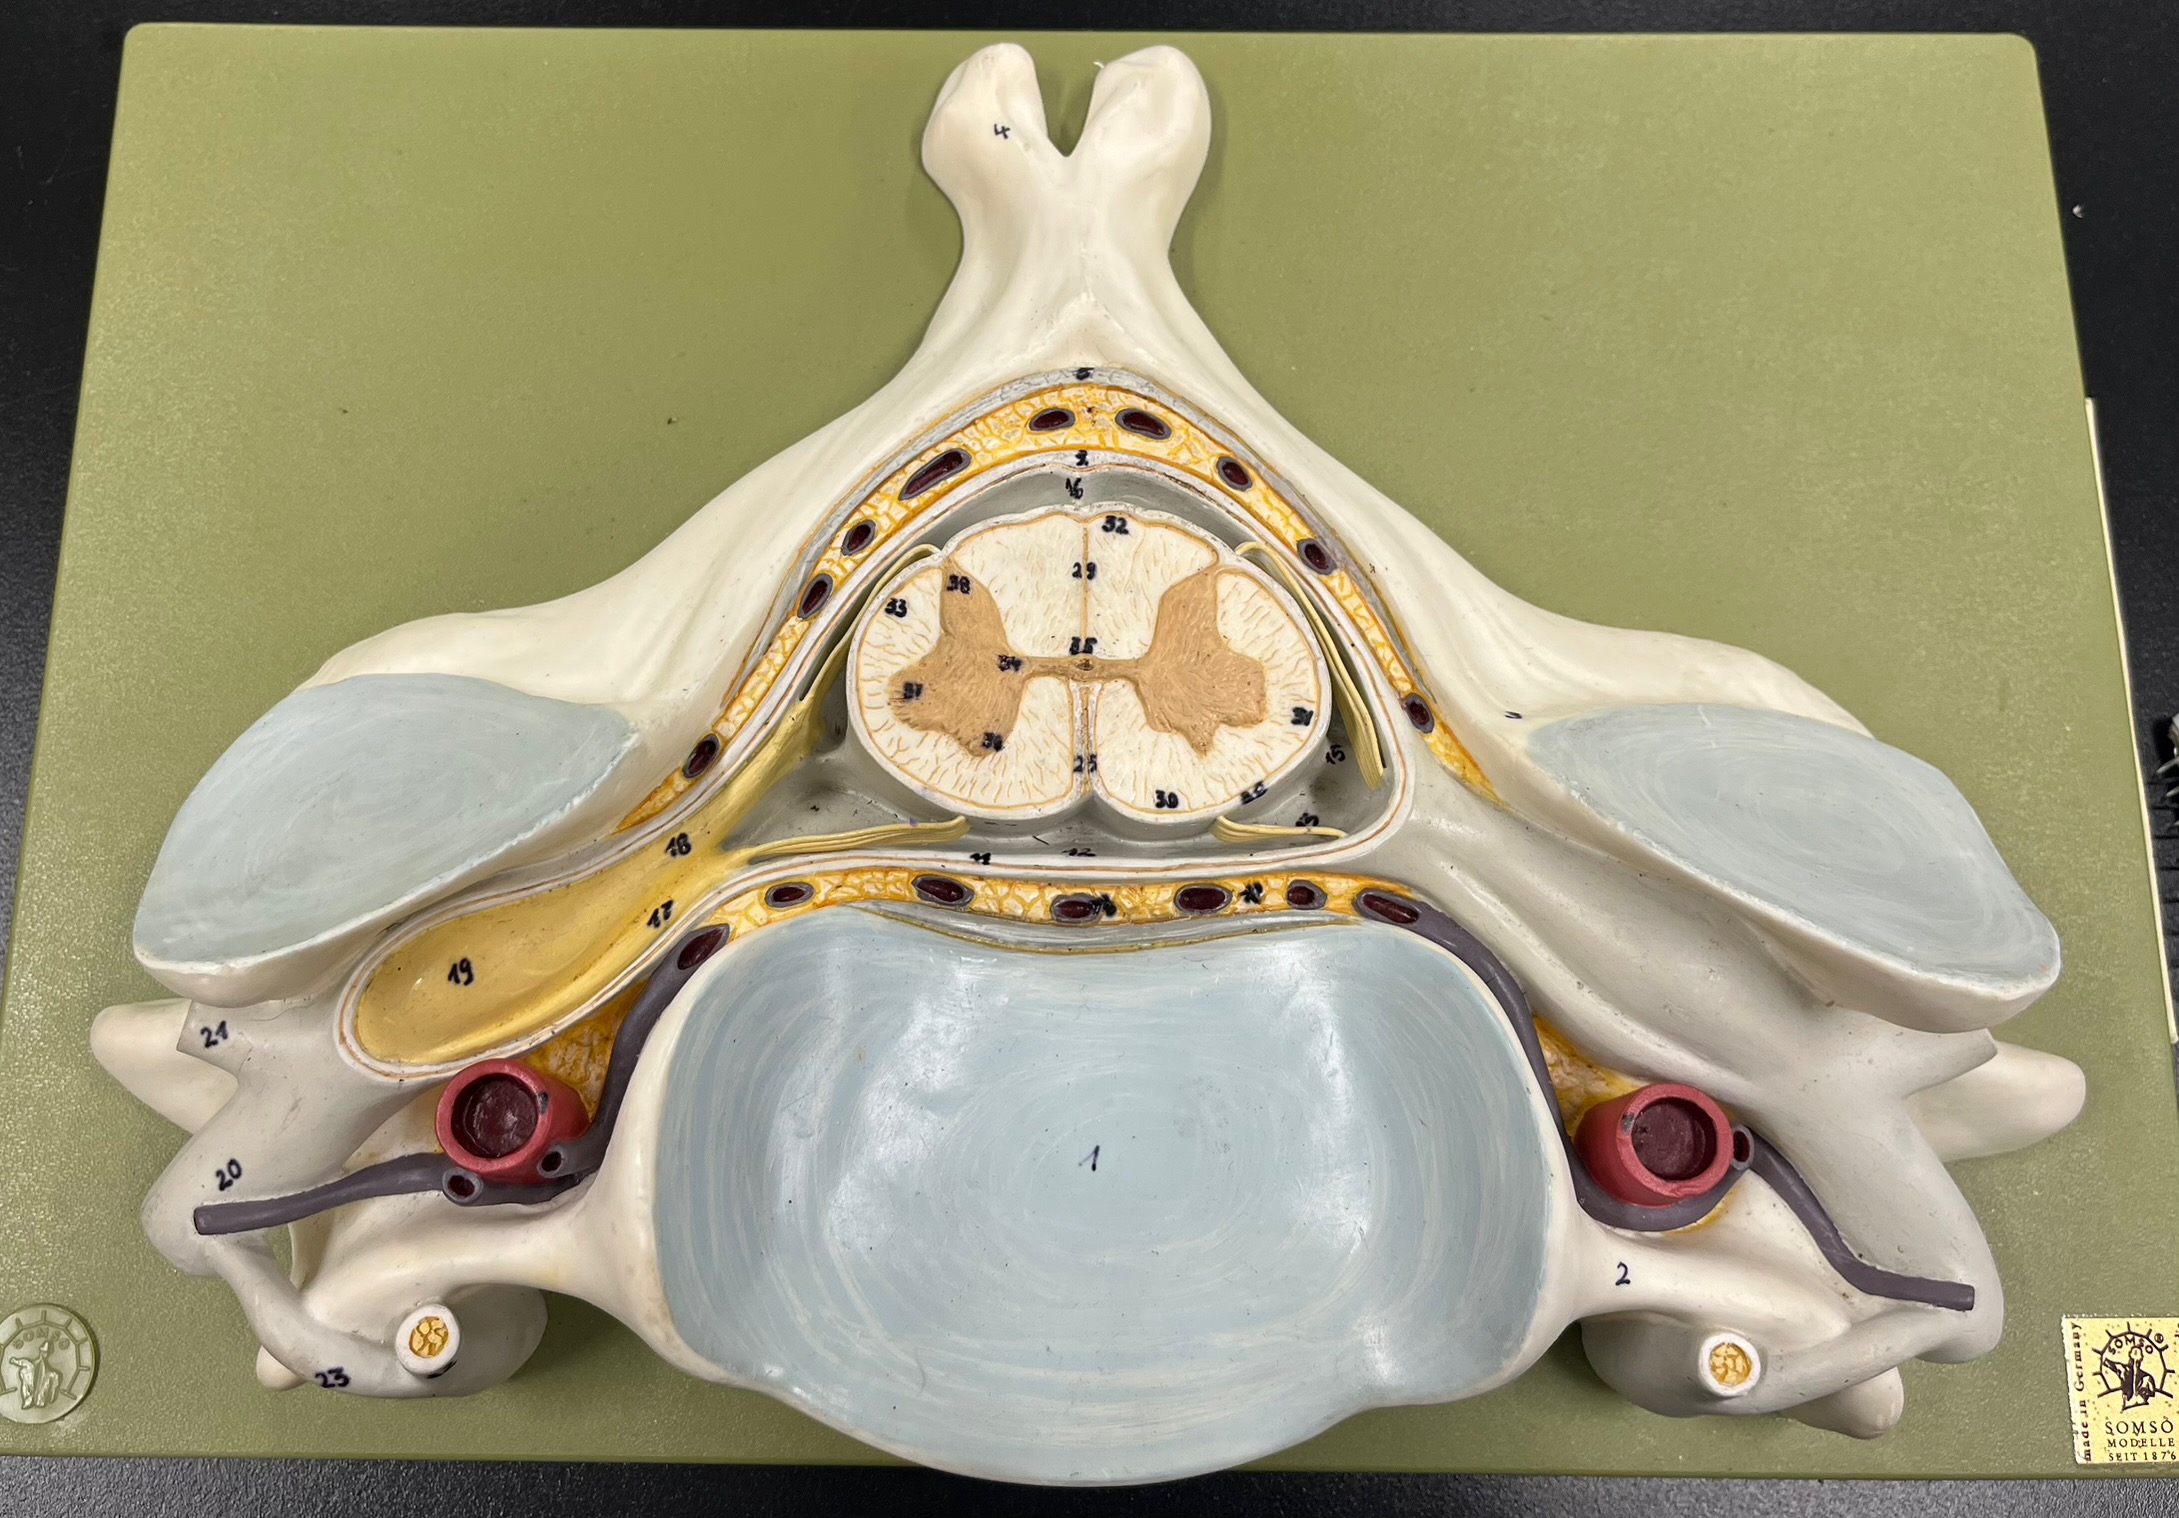

epidural space

dura mater

subdural space

arachnoid mater

subarachnoid space

pia mater

denticulate ligaments

What is the groove here?

anterior median fissure

posterior median sulcus

posterior (dorsal) horn

posterior (dorsal) horn; R—>L

anterior (ventral) horn

lateral horn (selected models)

gray commissure

central canal

anterior column

lateral column

posterior column

white commissure

posterior (dorsal) root ganglion

What is the bulb here?

posterior (dorsal) root ganglion

posterior (dorsal) root

posterior (dorsal) root

anterior (ventral) root

anterior (ventral) root

dorsal ramus

dorsal ramus

ventral ramus

ventral ramus

rami communicantes

rami communicantes

sympathetic chain ganglia

sympathetic chain ganglia